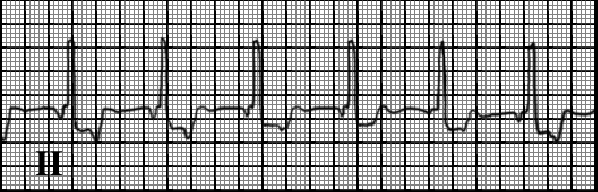

You are incorrect - our patient's rhythm strip shows atrial fibrillation.

The characteristic features demonstrated here include regular P waves associated with each QRS, with the P waves negative in lead II due to retrograde atrial conduction; a constant PR interval; and a rate ranging from 60 to 100 beats per minute.

In some cases, the P wave follows the QRS, as the atrium is depolarized after the ventricle. In other cases, no P wave is seen, as depolarization is concurrent.